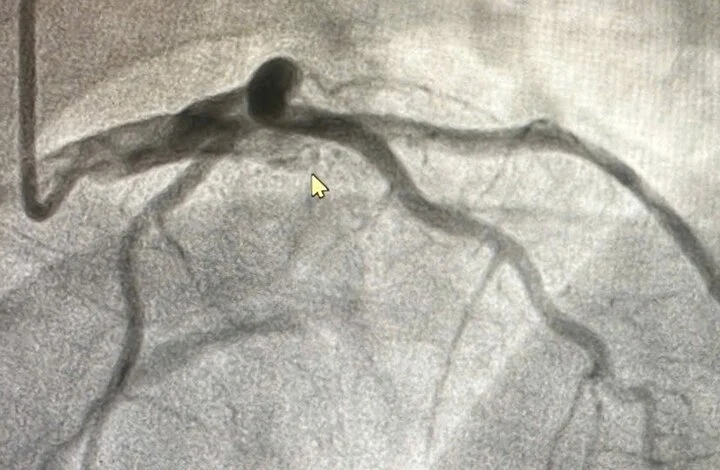

Khi chụp mạch vành, bác sĩ phát hiện tắc cụt hoàn toàn động mạch liên thất trước từ đoạn đầu, diện nhồi máu rất lớn, lý giải phần nào cho việc bệnh nhân đi vào sốc rất sớm.

Hình ảnh tắc cụt hoàn toàn động mạch liên thất trước từ đoạn đầu, diện nhồi máu rất lớn. (Ảnh: BVCC)